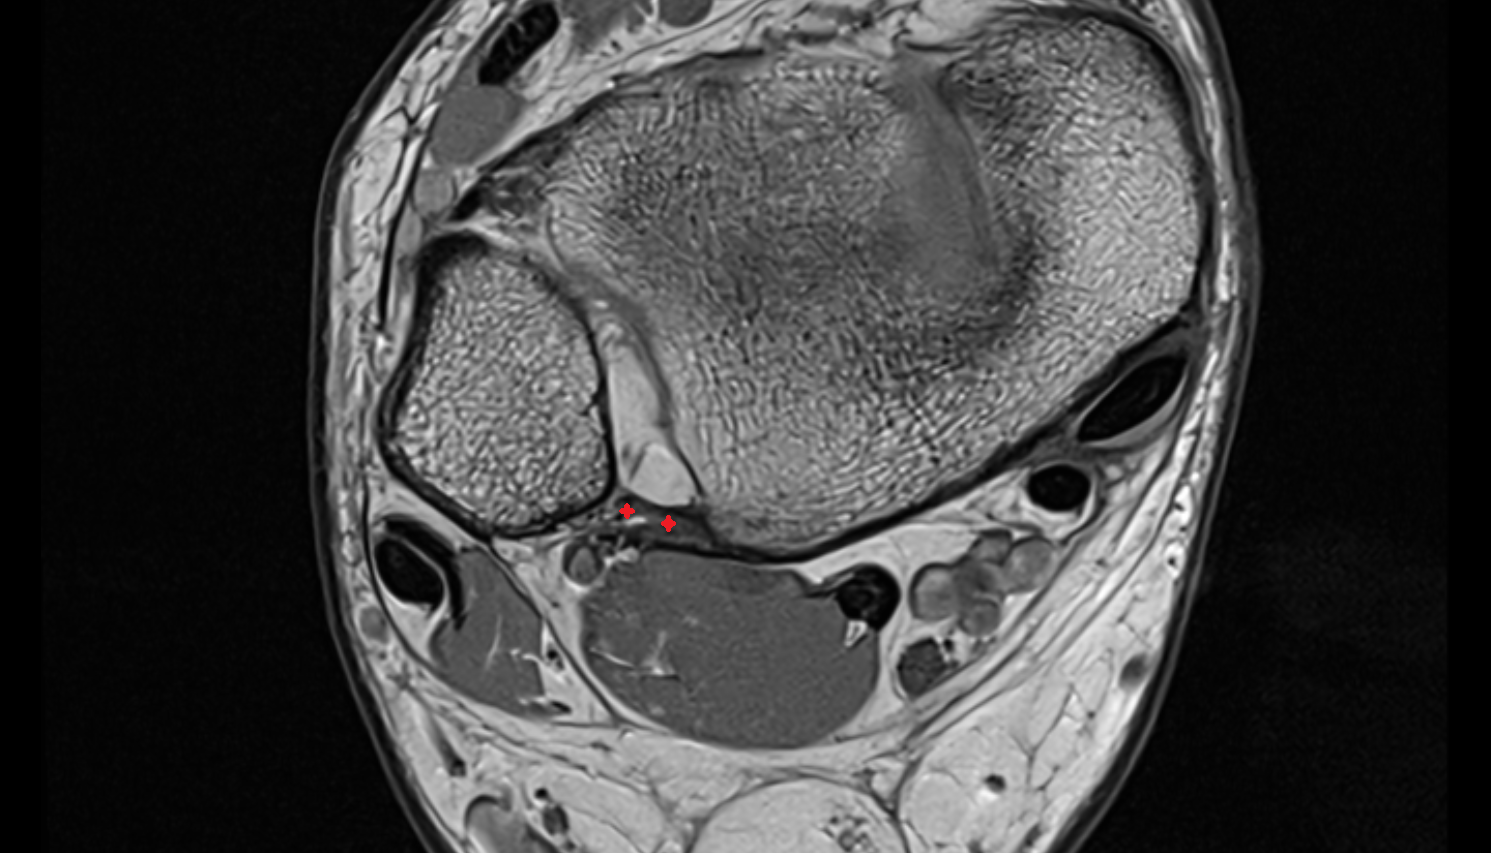

- Talus

- Head of talus

- Body of talus

- Neck of talus

- Calcaneus

- Anterior process of calcaneus

- Sustentaculum tali

- Ankle joint

- Talocalcaneal joint

- Talocalcaneonavicular joint